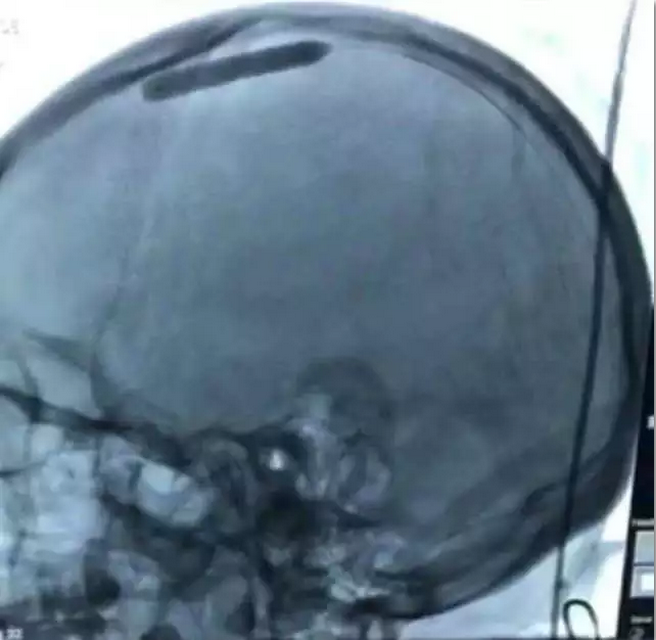

术前DSA造影显示:静脉循环时间明显延长,上矢状窦、窦汇及右侧横窦显影欠佳。

术后DSA造影结果:上矢状窦较前明显通畅